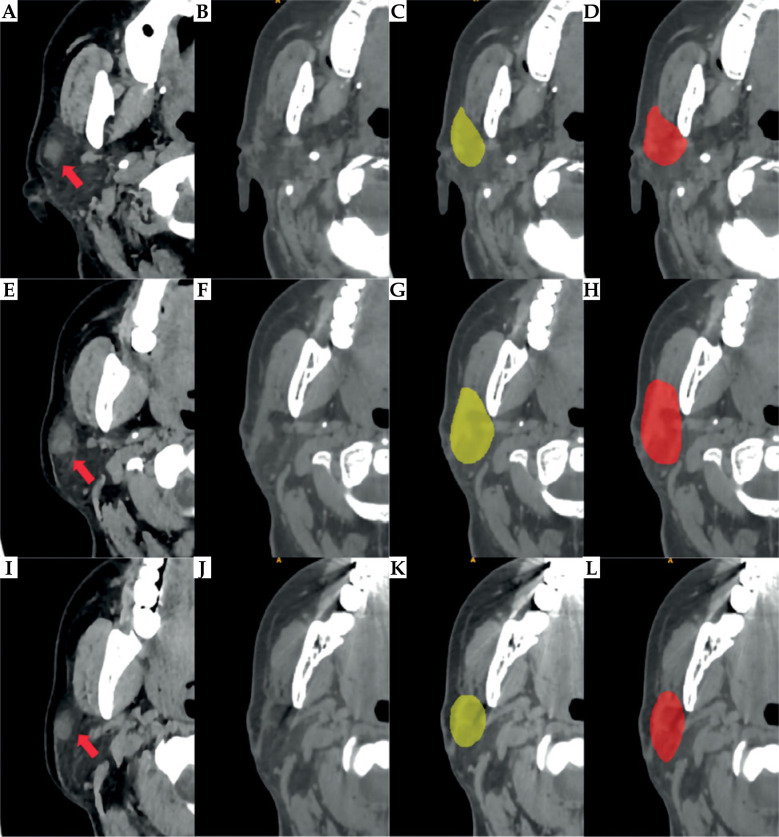

Material and methods: Using clinical imaging data from 326 patients with parotid gland carcinoma treated at Peking University School and Hospital of Stomatology between 2017 and 2023, we established a training dataset of 213 cases, a validation set of 53 cases, and a test set of 60 cases. The CTVs on the images were segmented using 3D Res-UNet, a deep learning model, and compared against manual delineations performed by experienced radiation oncologists. The performance of 3D Res-UNet was optimized through a comprehensive preprocessing and training process tailored to the dataset's characteristics.

Results: The deep learning model yielded a significant improvement in segmentation efficiency. The deep learning model generated initial CTV contours in 9.4 seconds of computational time. Subsequent expert review and minor adjustments required an average of 11.9 minutes, substantially shorter than the 46.7 minutes needed for fully manual delineation. Quantitative analysis showed that the Dice similarity coefficient (DSC) of automatic segmentation by 3D Res-UNet was 0.709, which improved to 0.924 after expert review. Qualitative evaluation by senior oncologists further affirmed the clinical acceptability of the automatically segmented CTVs.